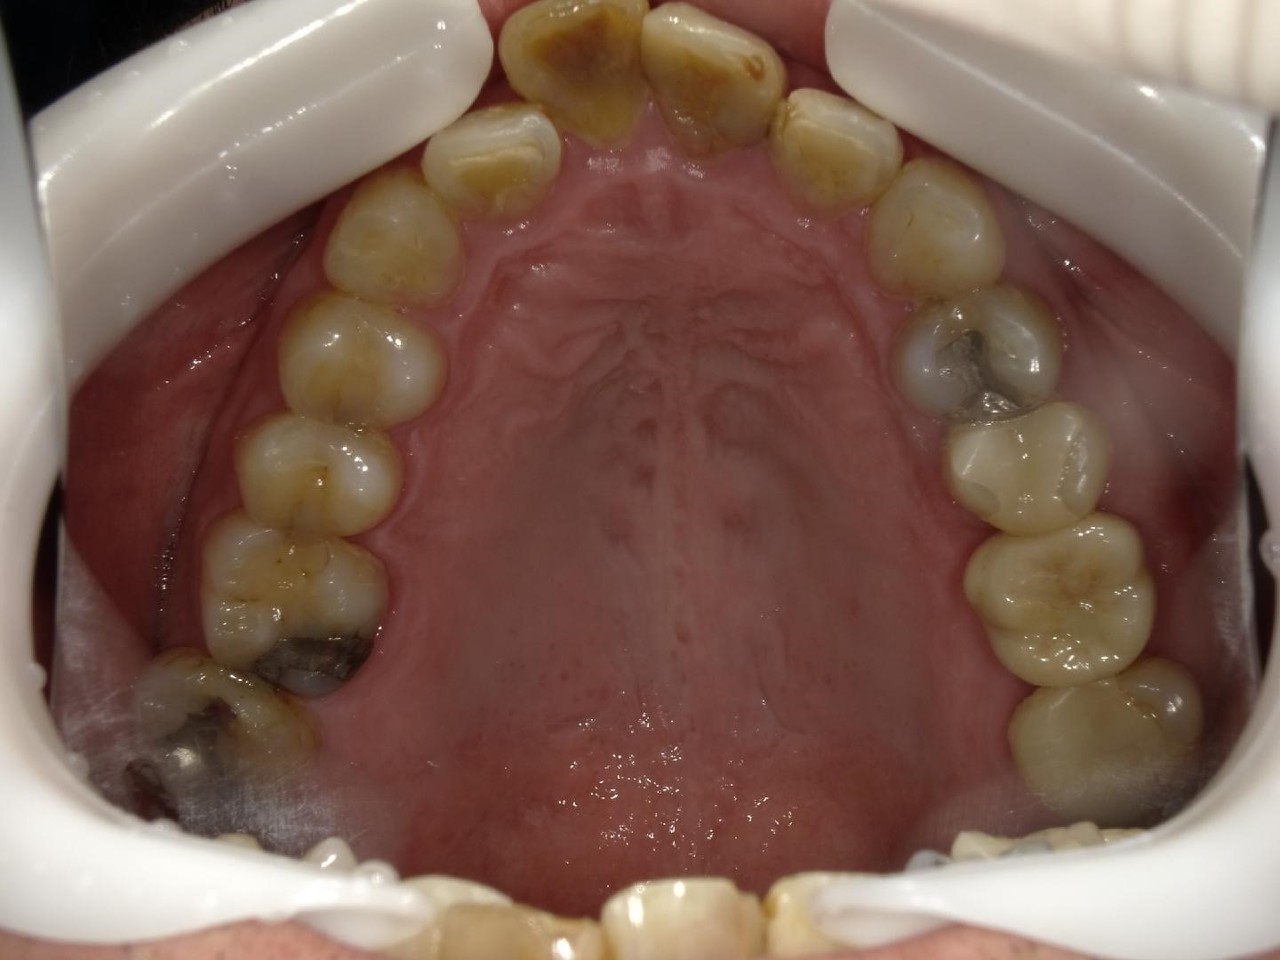

1.左上3番 インプラント抜歯即時埋入即時荷重(手術当日に抜歯を行い、当日に仮歯を入れています。)、左上4番 3ユニット式ブリッジが入るまでの暫間インプラントを埋入して当日に仮歯の装着。 左上5 既存骨3mmのグラフトレスサイナスリフト。最終補綴は、3ユニットジルコニアブリッジで治療を終えた症例

Before

枚方市のインプラントの症例

E・S様 女性 60代

患者様の症状としては、左上5番の排膿と重度の歯の動揺、重度の骨吸収、左上3番、中程度の骨吸収と中程度の歯の動揺、自発痛がありました。

治療法としては、左上3456にブリッジ治療が行われていたが、左上5の骨吸収と排膿を認めるために抜歯を行った2か月後に、患者様は、インプラント治療を希望。左上3の骨吸収と動揺も認めていたために、左上3を保存しても将来的な抜歯が予想されたため、左上3抜歯しての左上345の3ユニット式ブリッジ治療の計画を立てインプラント手術を行っています。患者様は、前歯がないことを気にされていたため、左上3番の抜歯と同時の仮歯製作と左上4番暫間インプラントにての仮歯製作を手術と同時に行っています。また、左上3番の歯肉退縮を予防するために、ご自分の歯の一部を温存するルートメンブレンテクニックを行っています。左上5に関しては、既存骨が3mm程度しかないので、グラフトレスサイナスリフトを施行して、表面の骨吸収した部分に骨補填材填入して、ボリュームを維持させていただいています。最終的な3ユニットブリッジは、ジルコニアで製作しています。補綴物の製作に関しては、オールデジタルで行っています。

治療結果は、患者様の希望通り、見えるところの歯がない状態なく、治療を終えることができたことと、また、グラフトレスサイナスリフトを施行することにより、従来のサイナスリフトを施行した場合と比較して、6時か月以上早く治療を終えることができたことと、ルートメンブレンテクニックを行うことで、歯肉退縮を少なくでき、自然な見た目で、最終補綴物を装着できました。従来のGBRやサイナスリフトを行わなかったことにより、短時間で、低侵襲に治療を終えることができ、審美面と機能面の回復を行うことができました。

治療の期間・回数:4か月、10回

治療の価格:814,000円(税込)

治療費の内訳:インプラント基本料(フィックスチャー及び手術費用、投薬費用、レントゲン費用、インプラント上部費用(アバットメントおよびジルコニアクラウンの費用用)右上3番5番 330000円×2 660000円(税込み)オプション費用 右上5グラフトレスサイナスリフト費用 33000円(税込み) 右上3抜歯即時荷重費用 33000円(税込み) 暫間インプラント費用 0円

治療のリスクや副作用:手術後に、痛みや腫れ、出血、合併症などを引き起こす可能性があります。噛む感覚がご自身の歯と異なる場合があります。見た目がご自身の歯と異なる場合があります。手術後にメインテナンスを継続しないと、インプラントが抜け落ちる可能性があります。